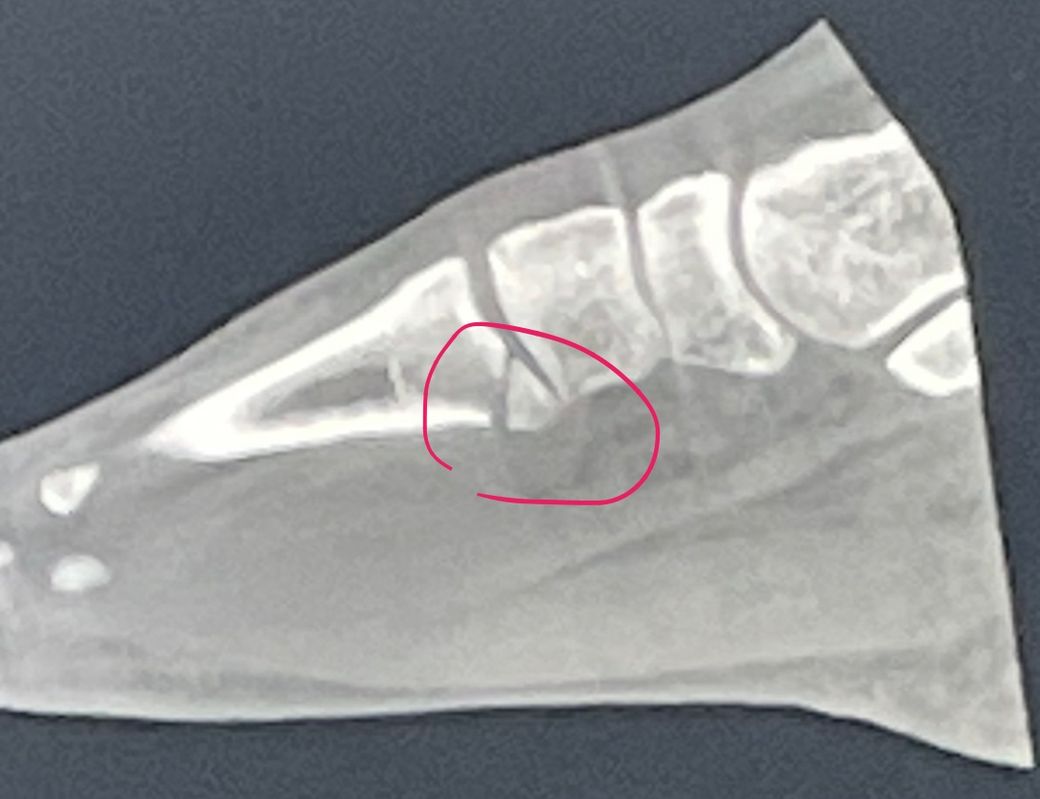

중족골 골절 부정유합이 되어도 괜찮나요?

안녕하세요 현재 중족골 골절 3주차입니다.

병원에서 말하기를 안쪽이 부러져 수술이 어렵다고 비수술로 진행하자고 하네요.

근데 사진상에는 정확하게 나와있지않지만 뼈가 깔끔하게 부러지지 않고 살짝 어긋난채로 부러졌습니다.

그러면서 병원에서 말하길 부정유합인채로 붙는다고 하면서 어쩔수 없는 불편함은 감내하라고하는데

이게 맞나싶네요.. 수술 안해도 괜찮나요..?

• 1번 째 사진

병원에서 말씀하신대로 안쪽 골절로, 수술이 어렵고 수술 시행 후 예상되는 부작용도 더 큰 상태로, 깁스 하시면서 유합이 되는 것을 기다리시는 것을 권유드립니다.